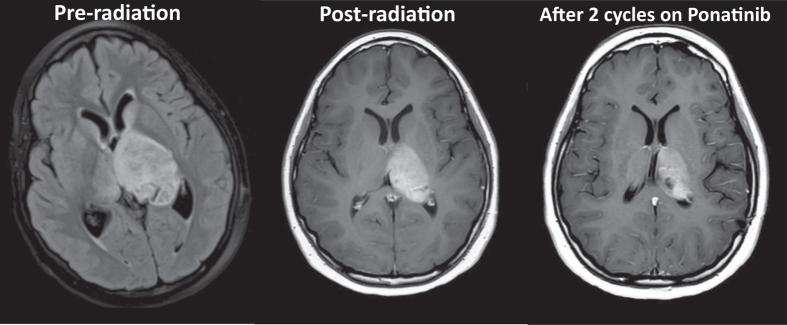

Approximately 1-5% of pediatric intracranial tumors originate in the thalamus. While great strides have been made to identify consistent molecular markers in adult oligodendrogliomas, such as the 1p/19q co-deletion, it is widely recognized that pediatric oligodendrogliomas have a vastly different molecular make-up. While pediatric thalamic or "central oligodendrogliomas" are histologically similar to peripheral pediatric oligodendrogliomas, they are behaviorally distinct and likely represent a cohesive, but entirely different entity. We describe a case of a 10-year-old girl who was diagnosed with an anaplastic glioma with features consistent with the aggressive entity often diagnosed as central or thalamic oligodendroglioma. We performed whole-exome (paired tumor and germline DNA) and transcriptome (tumor RNA) sequencing, which demonstrated an fusion. We describe this fusion and our rationale for pursuing personalized, targeted therapy for the patient's tumor that may potentially play a role in the treatment of similar cases.